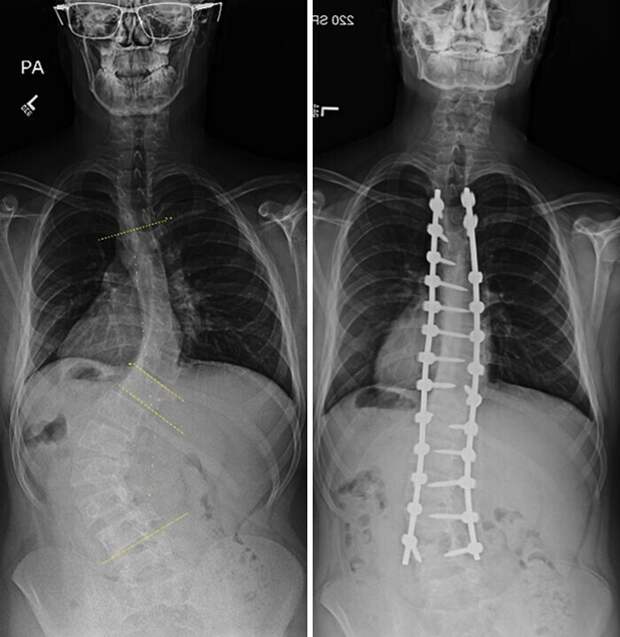

Операция по поводу искривления позвоночника: до и после